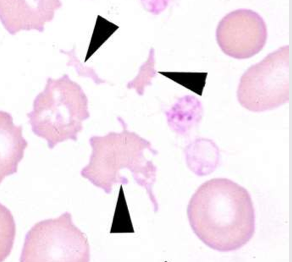

What cell is this ?

Acanthocyte

Schistocytes